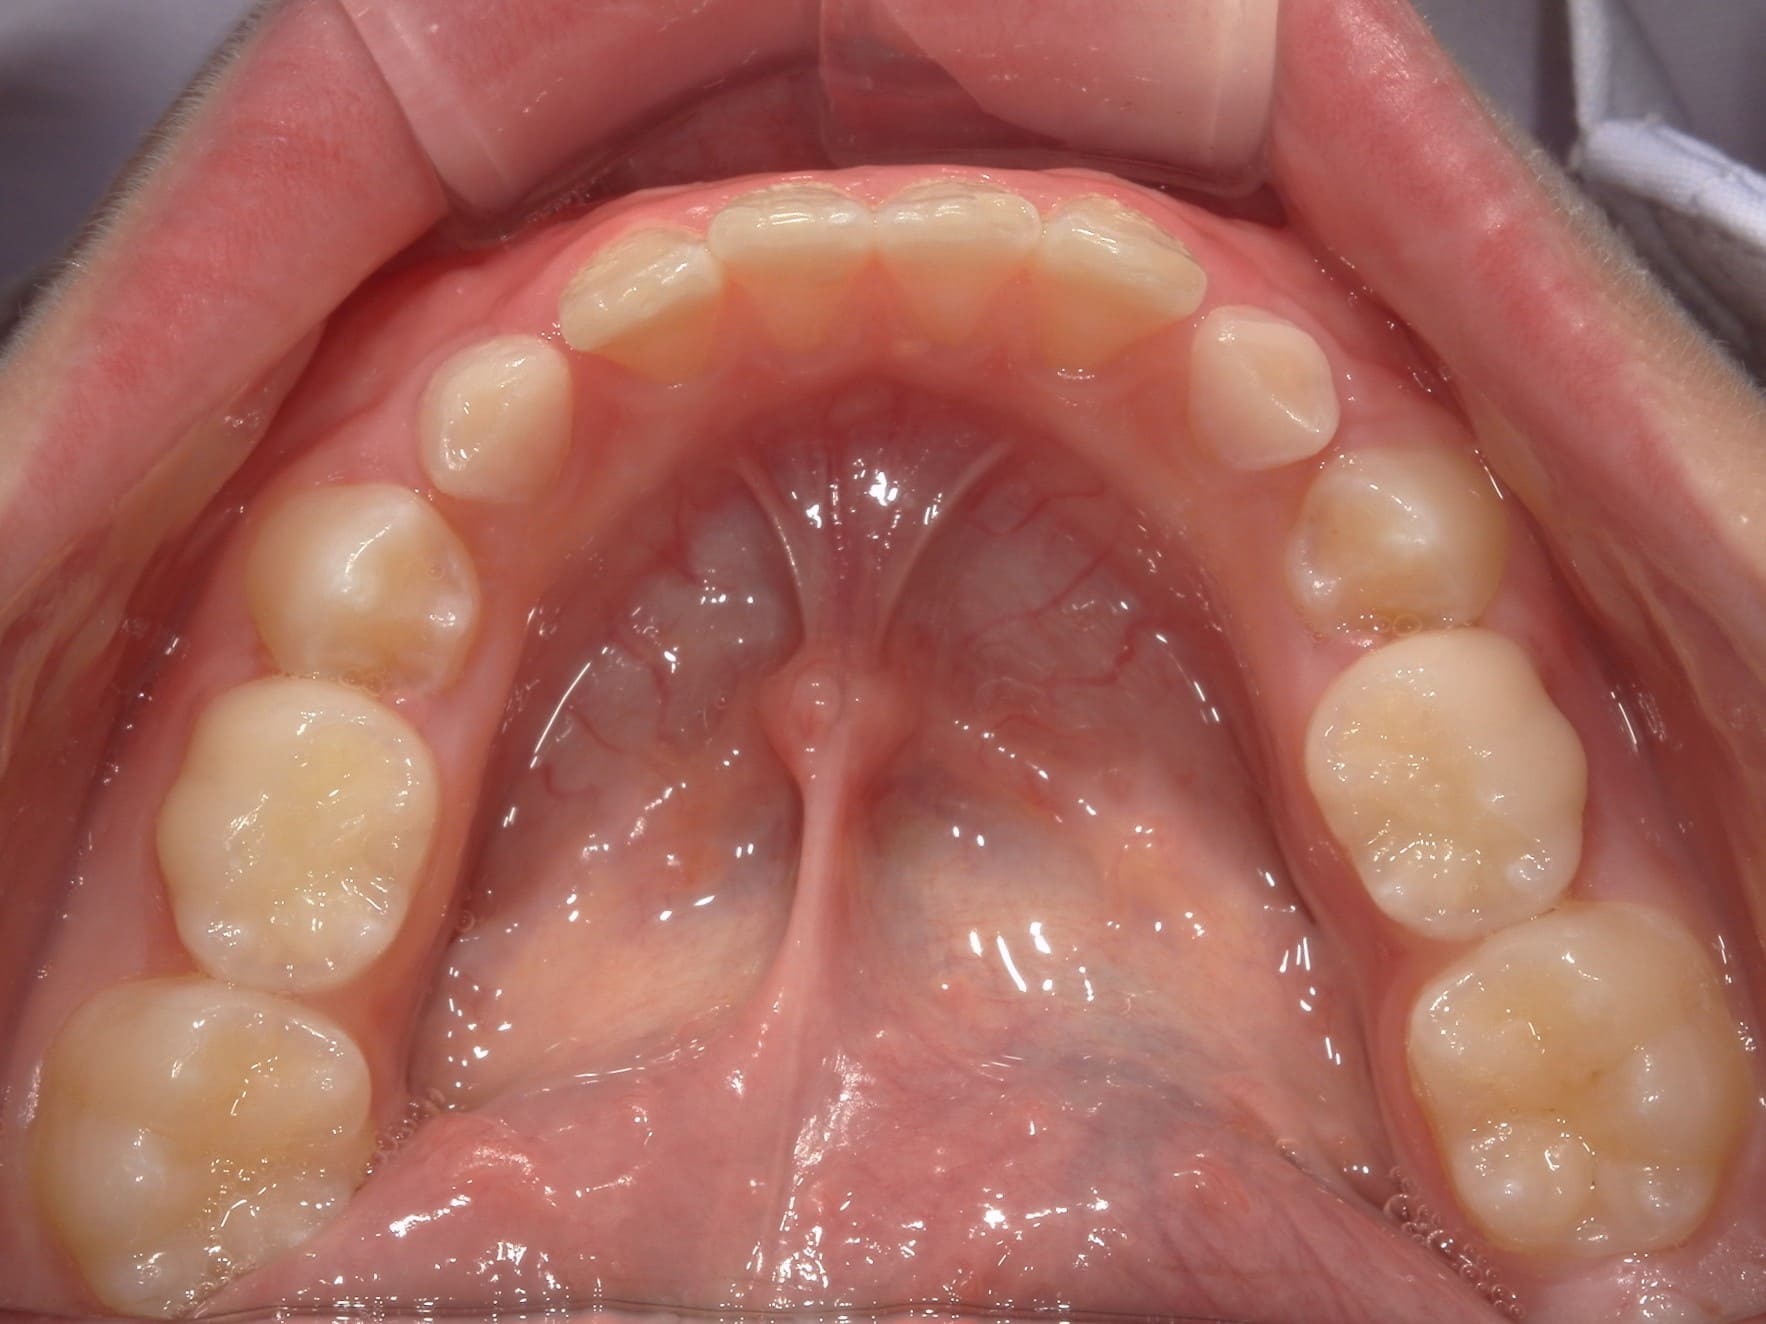

| 主訴 | 歯の生えるスペース不足が懸念され、歯列の乱れ(叢生)を整えるために来院された患者様です。 |

| 治療期間・回数 | 1年3ヶ月・11回 |

| 費用 | 420,000円(税別) |